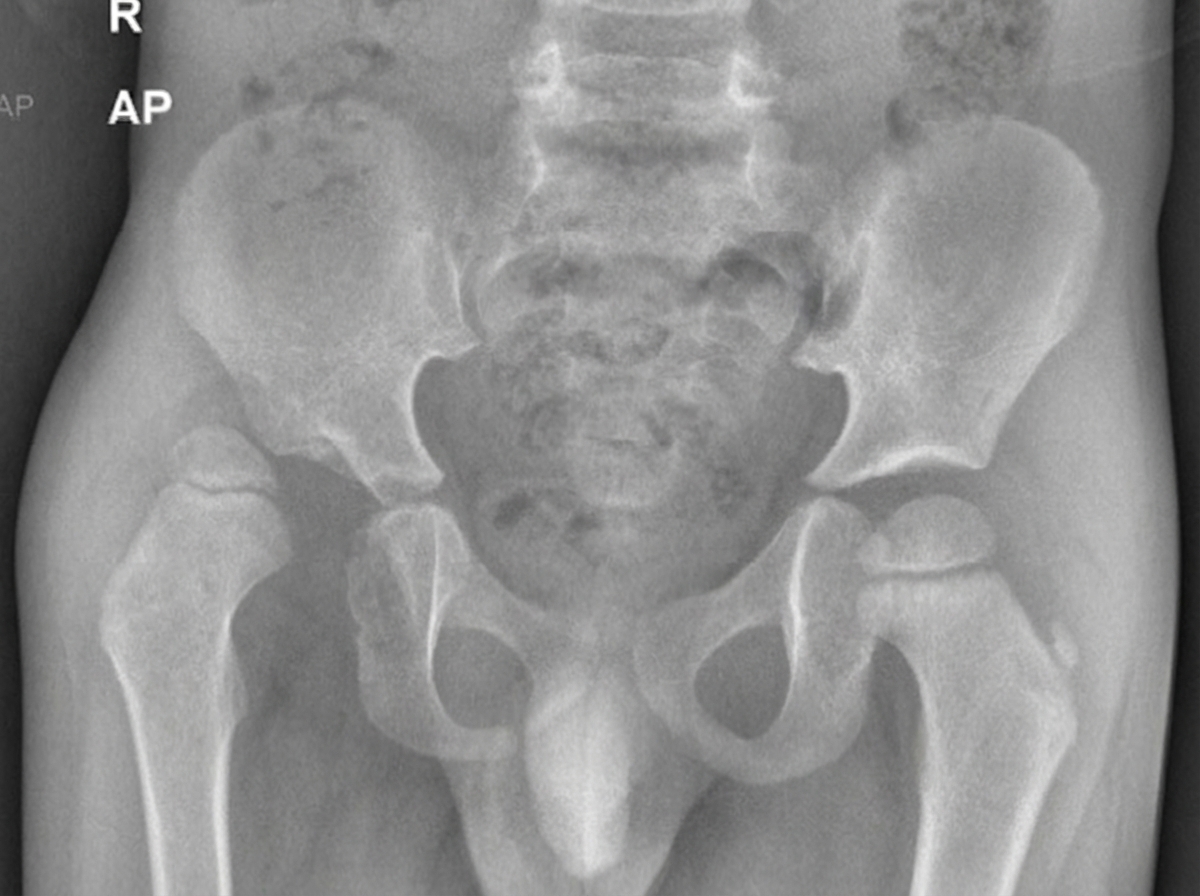

Explanation: **Explanation:** The clinical presentation of an **obese adolescent** with chronic hip pain, limping gait, and **hypothyroidism** is a classic "textbook" description of **Slipped Capital Femoral Epiphysis (SCFE)**. In SCFE, the femoral head slips posteriorly and inferiorly relative to the femoral neck through the growth plate. **Why USG is the correct answer (of no use):** While Ultrasonography (USG) can detect a joint effusion or a subtle step-off at the head-neck junction, it is **not a standard diagnostic tool** for SCFE. It lacks the sensitivity and specificity required to grade the slip or plan surgical management. In the context of NEET-PG, USG is the "least useful" investigation compared to radiographic imaging. **Analysis of other options:** * **X-ray (Option A):** This is the **initial and gold standard investigation**. AP and Frog-leg lateral views are essential. Key signs include **Klein’s Line** (which fails to intersect the femoral head) and the **Steel Sign** (double density). * **MRI (Option B):** Highly sensitive for diagnosing **"Pre-slip" SCFE** (where there is physeal widening and edema but no displacement yet) and for assessing femoral head vascularity (AVN). * **CT (Option C):** Useful for complex cases to accurately measure the degree of posterior tilt and for preoperative planning of corrective osteotomies. **Clinical Pearls for NEET-PG:** * **Associations:** SCFE is strongly associated with endocrine disorders like **Hypothyroidism** and Growth Hormone deficiency, especially when bilateral or presenting at an atypical age (<10 or >16 years). * **Drehmann Sign:** Positive (obligate external rotation of the hip during passive flexion). * **Treatment:** The definitive management is **In-situ pinning** (usually with a single cannulated screw) to prevent further slippage.

Explanation: ***Developmental dysplasia of the hip (DDH)*** - Most common cause of **painless limp** in toddlers aged **1-3 years**, presenting with **leg length discrepancy** and **asymmetric hip abduction**. - Radiological findings include **shallow acetabulum**, **lateral displacement of femoral head**, **disrupted Shenton's line**, and **elevated acetabular index**. *Septic arthritis* - Presents as an **acute febrile illness** with **severe hip pain**, **inability to bear weight**, and **systemic toxicity**. - Patient would appear **unwell** with **raised inflammatory markers** (CRP, ESR, WCC), which is not described here. *Slipped capital femoral epiphysis* - Typically occurs in **adolescents** aged **10-16 years**, especially those who are **obese** or have **endocrine disorders**. - Presents with **hip or knee pain** that worsens with activity, not typically seen in **3-year-olds**. *Perthes' disease* - Most commonly affects children aged **4-8 years**, with peak incidence around **5-6 years**. - Involves **avascular necrosis of femoral head** causing **progressive hip pain** and **restricted range of motion**, rare in **3-year-olds**.